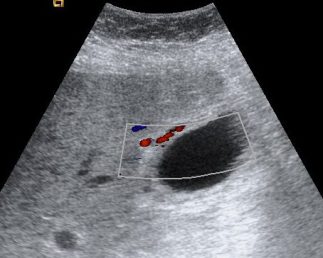

Se realiza ecografía abdominal:

En sucesivos cortes observamos lo siguiente:

Se observa una mala evolución radiológica. Dada la clínica del paciente y los hallazgos ecográficos podemos concluir que estos hallazgos son compatibles una colecistitis xantunogranulomatosa litiásica sobreinfectada (que se confirmó posteriormente con anatomía patológica).

- Colecistitis xantunogranulomatosa: nódulos o bandas intramurales. Se producen por la oclusión de los senos de Rokitansky Aschoff de la pared, los cuales se rompen, luego la bilis coloniza la pared y finalmente produce una reacción inflamatoria a la que puede sobreañadirse una infección. Es un factor de riesgo para el carcinoma.

- Eco y TC: Litiasis + engrosamiento mural focal o difuso. Puede haber cambios inflamatorios pericolecísiticos. Los nódulos hipocogénicos o bandas pueden sugerir el diagnóstico específico de c. xantunogranulomatosa.

- El diagnóstico raramente se realiza previo a la cirugía y al análisis histopatologíco.